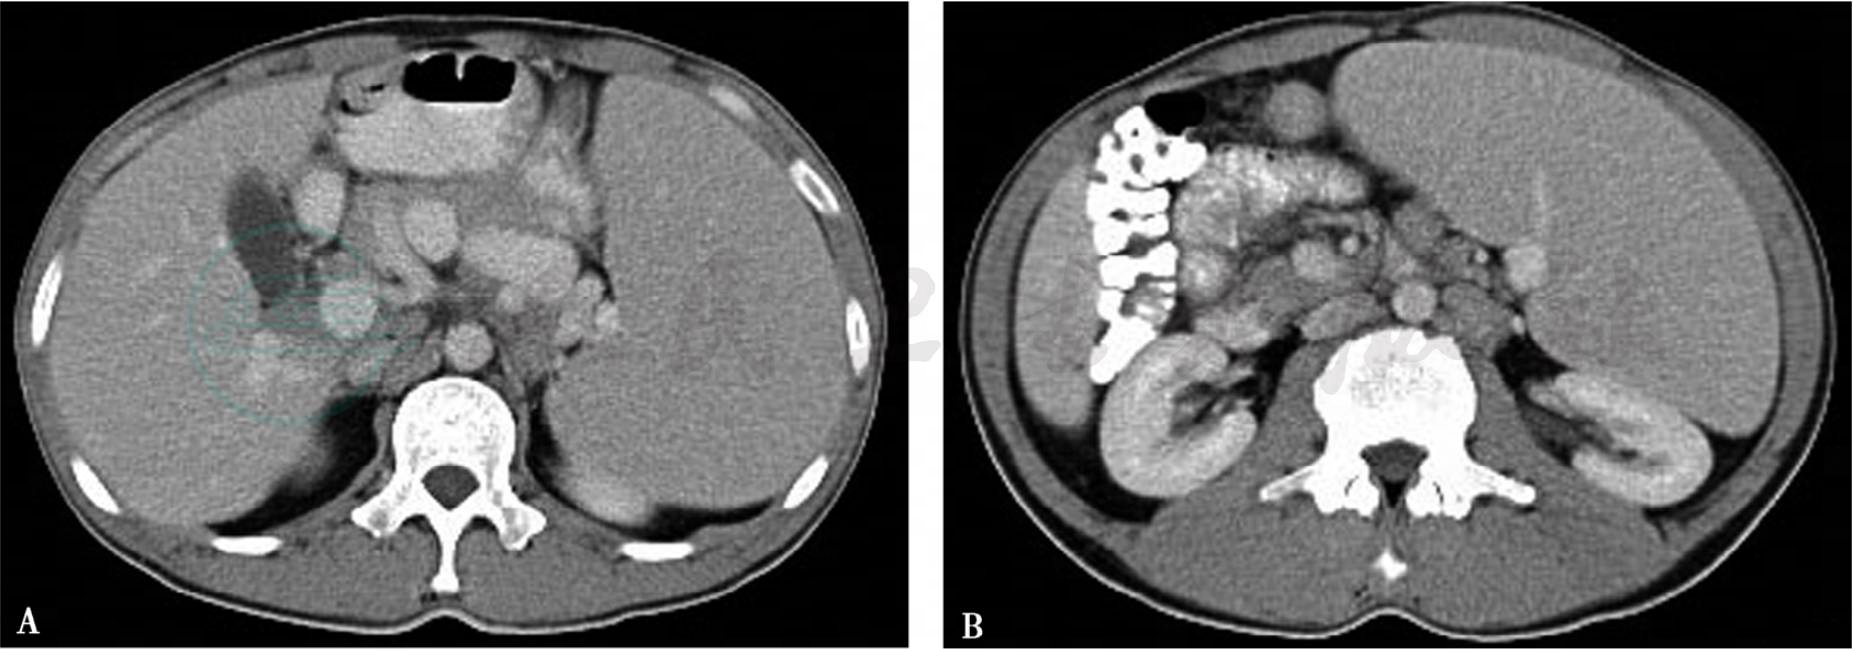

图1 男性,40岁NHL,弥漫大B细胞

A、B.上腹部CT增强扫描,显示脾脏明显肿大,超过肝脏下缘,密度尚均匀。腹膜后可见肿大淋巴结,左肾受压改变

当超声、CT及MRI显示脾脏病变合并腹膜后、脾门、肝门及胰周肿大淋巴结时,对诊断是有一定帮助的(图1~图3),特别当肿大淋巴结位于肾门水平以下时,因为转移性淋巴结肿大很少累及肾门水平以下。